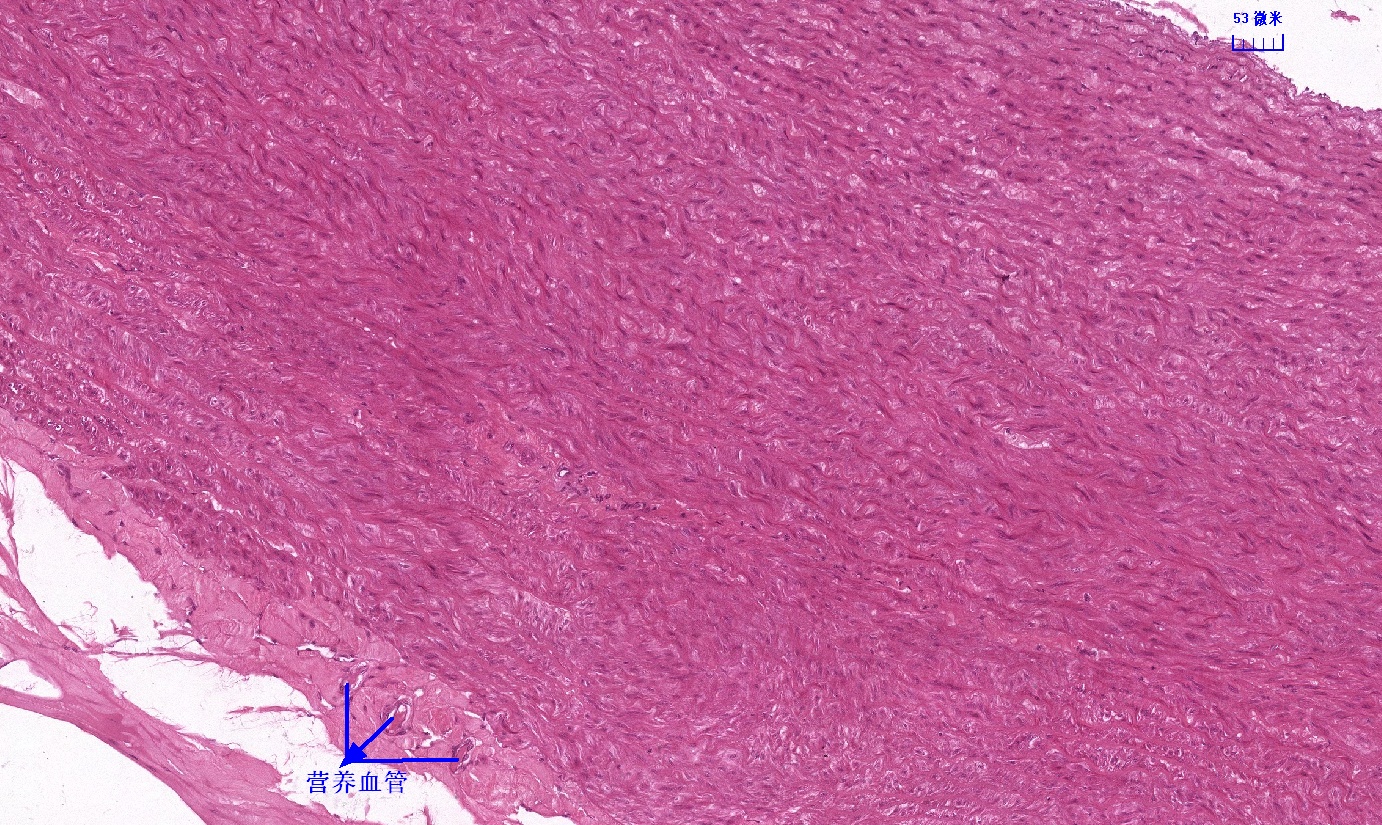

6.1 循环系统切片库